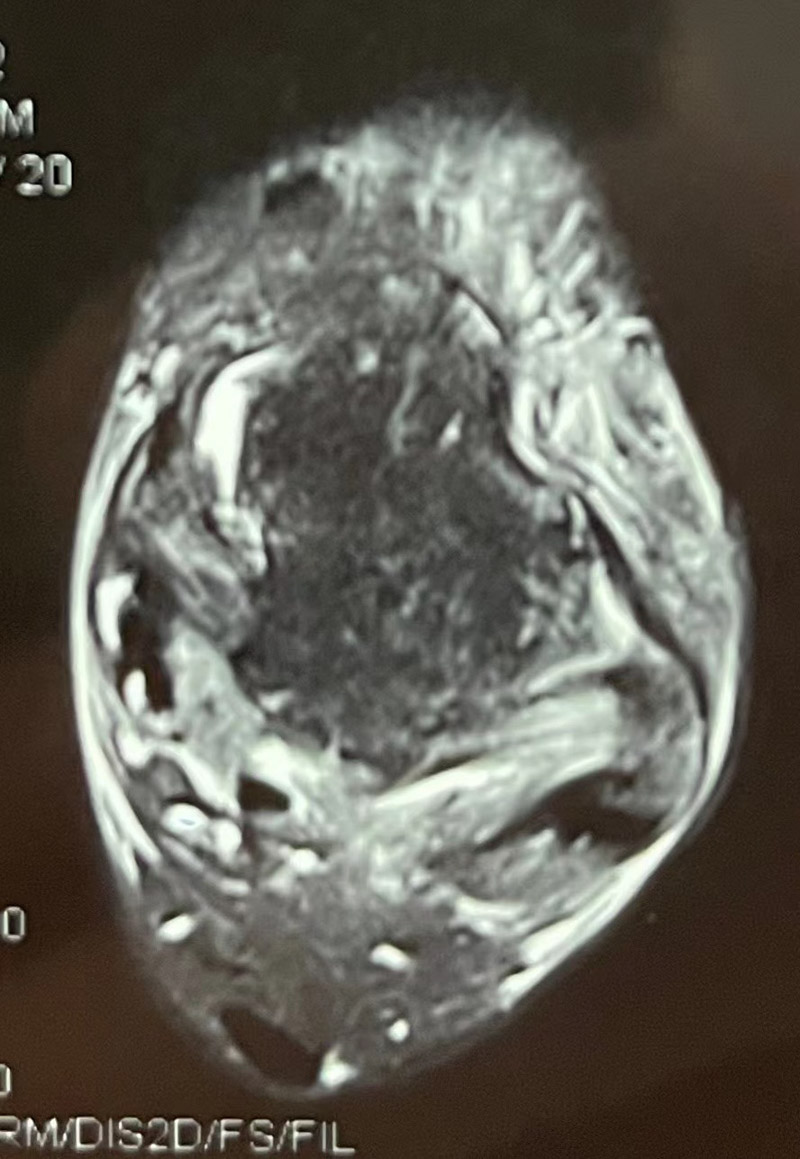

▲行韌帶修復術后

要解決童童關節失穩的問題,只能進行韌帶損傷修復手術治療。術中,韋釗嵐副主任運用關節鏡通過兩個微創口慢慢將撕裂的韌帶進行了縫合固定。經過手術,童童踝關節的穩定性明顯增強,術后第一天便可下地行走,行走時疼痛感也消失了。“以后我又能夠隨心所欲地練習跳舞了!”童童開心地說。